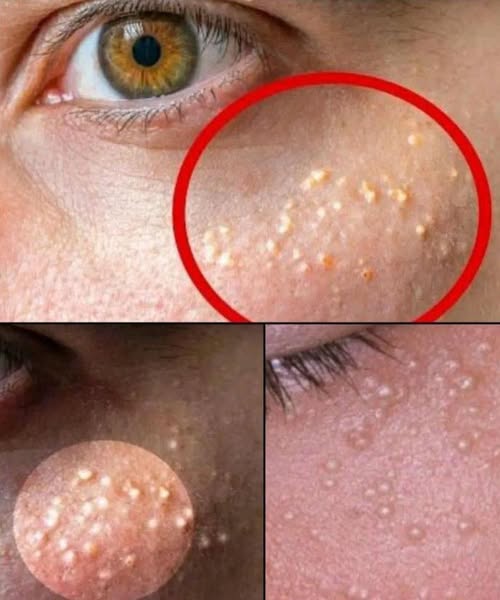

They often show up quietly—tiny, hard, pearl-white bumps clustered around the cheeks, eyelids, or nose. They don’t hurt, they don’t itch, and no matter how much you wash your face, they never seem to go away. For many people, these mysterious bumps can last for months… or even years. But what they mean may surprise you.

These small bumps are not pimples, and they’re not caused by dirt or poor hygiene. In most cases, they’re actually milia—tiny cysts formed when dead skin becomes trapped beneath the surface. Instead of shedding normally, it gets sealed under the skin, creating a firm, bead-like bump that refuses to pop.

While they’re completely harmless, their appearance can signal that your skin is struggling with something deeper. Dermatologists often point to several common triggers: heavy skin creams that clog pores, unexfoliated buildup, sun damage thickening the skin, or even long-term irritation around the eyes. In other cases, a sudden flare-up can be the body’s response to hormonal shifts, stress, or an impaired skin barrier trying to rebuild itself.

The good news? These bumps can be treated—but not by squeezing, which only leads to scarring. Milia need gentle correction: lighter skincare, better exfoliation, improved routines, and sometimes professional extraction. When handled properly, the skin smooths out again, revealing a clearer, healthier complexion.

Knowing what these bumps really mean is the first step—because your skin is always trying to tell you something.